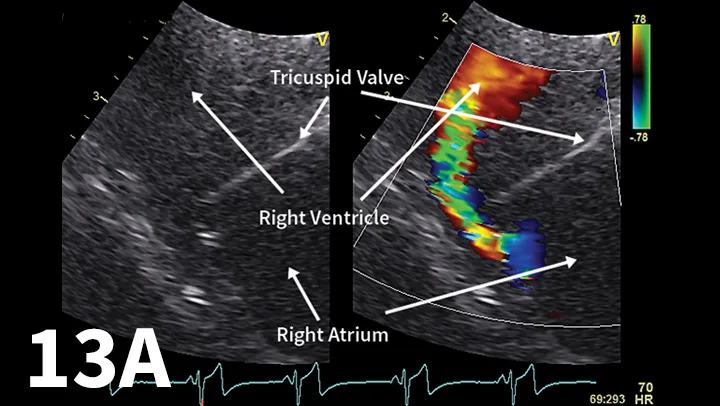

FIGURE 1

Right-sided 5-chamber long-axis view showing the left ventricular (LV) outflow tract. The LV is hypertrophied, and there is an obstructive ridge in the LV tract below the valve. (Ao = aorta; LA = left atrium)